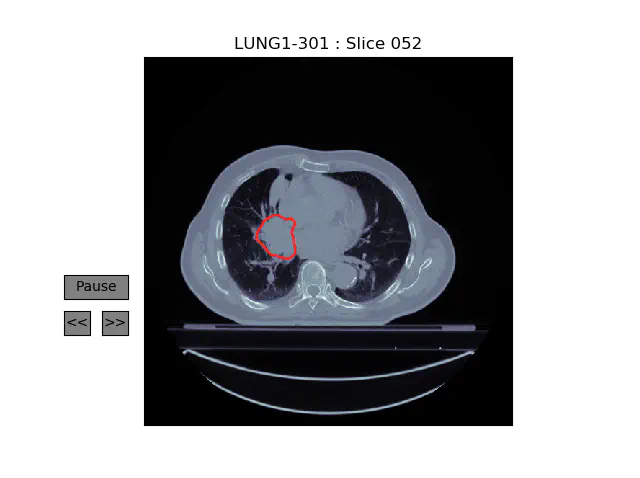

A Pipeline for Lung Tumor Detection and Segmentation from CT Scans Using Dilated Convolutional Neural Networks